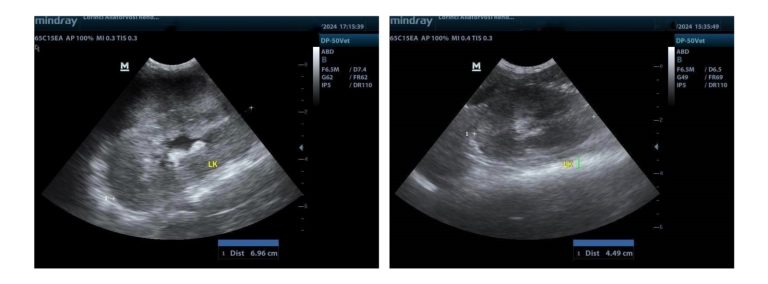

Limfómás vese ultrahang felvétele kezelés előtt és 1,5 hónappal a terápia megkezdése után

A medián túlélési idő átlagosan kb. 3-6 hónap. Korai felismerés és kedvező terápiás válasz esetén bizakodhatunk hosszabb túlélésben.